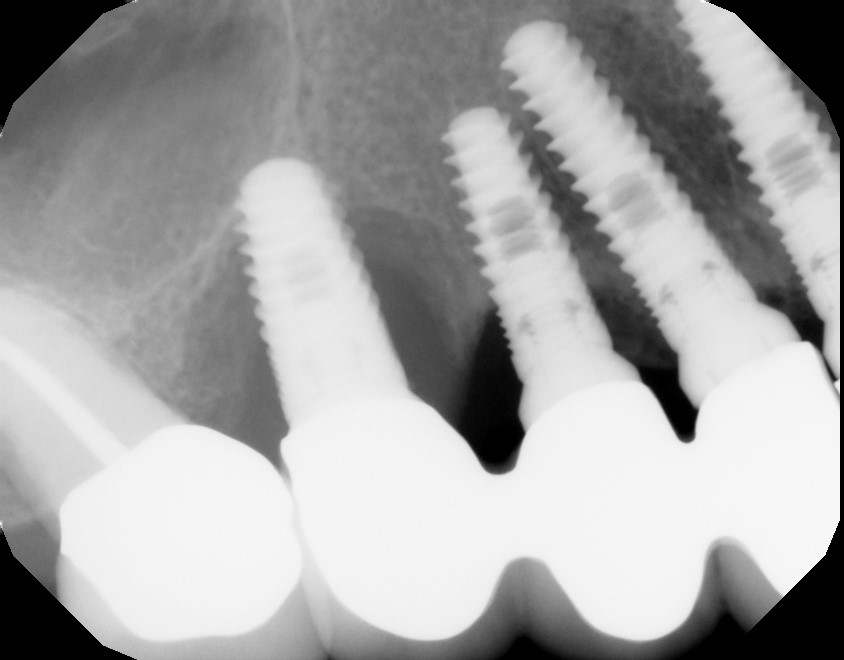

We at the Stuart Center for Laser Periodontics and Implants, welcome you to our practice. We are proud to serve the periodontal needs of people from Martin, St. Lucie, Palm Beach, Indian River, Vero Beach, Palm City, Port Salerno, Hobe Sound, Fort Pierce, Jensen Beach, West Palm, Gardens, Palm Beach, and Jupiter, FL. Dr. Nick DeTure is your Stuart periodontists, specializing in the treatment of gum disease. The Stuart Center for Laser Periodontics and Implants is a “state of the art” practice using the latest digital radiology, micro-surgery techniques and alternative treatments that are available. We pride ourselves in providing excellent, innovative and comprehensive care with compassion and understanding.